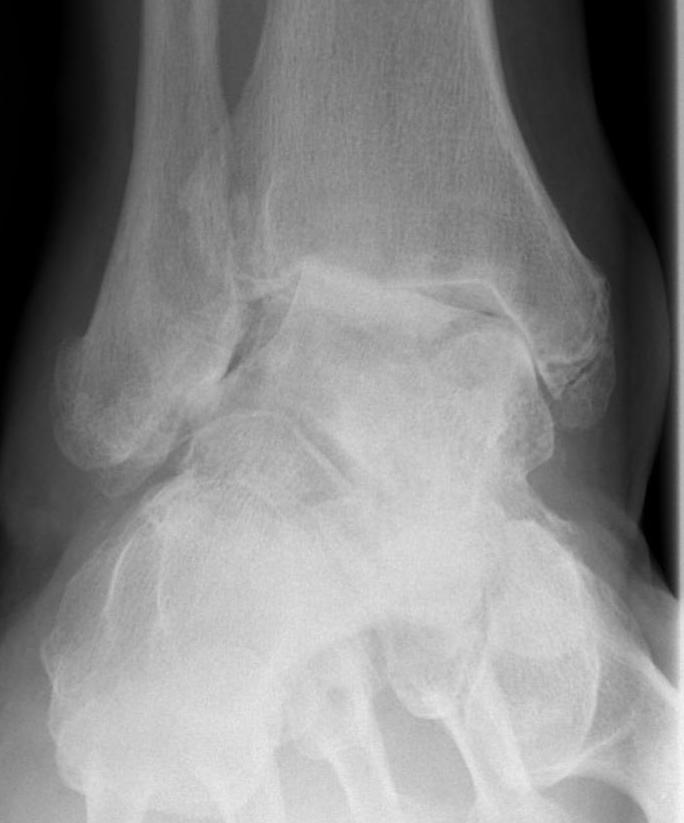

Stage 3 Tibialis posterior dysfunction / Rigid flatfoot

Options

Double (subtalar / TNJ) versus triple arthrodesis (subtalar / TNJ / CCJ)

- 23 feet with stage 3 T posterior dysfunction

- treated with double v triple arthrodesis

- no difference in outcomes

- shorter operative time with double arthrodesis

Burrus et al J Foot Ankle Surg 2016

- 16 rigid pes planus comparing double and triple arthrodesis

- increased nonunion and worse functional outcomes with double arthrodesis

Triple Arthrodesis